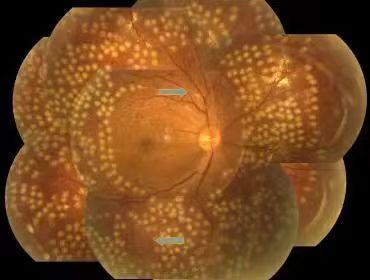

不同程度的糖尿病视网膜病变

全视网膜激光光凝术后